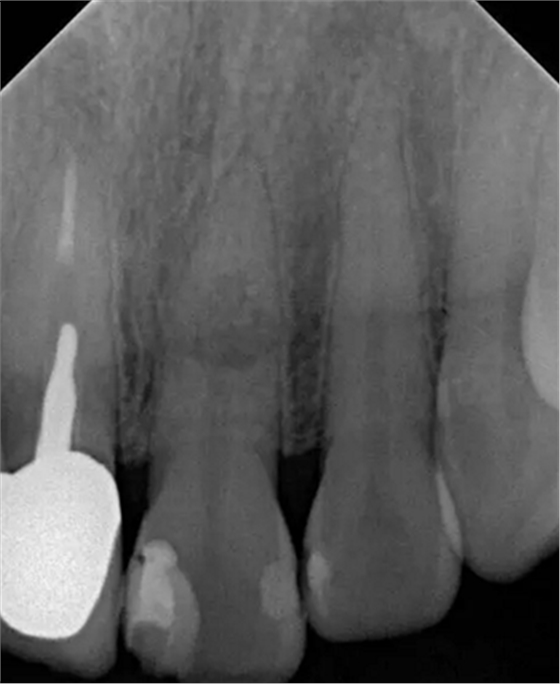

左上中切牙近遠中有牙色充填體,邊緣繼發(fā)齲,牙齒不松動,輕微叩痛,患牙冷測遲鈍,牙齦未見異常。X線片示:充填體周圍繼發(fā)齲壞近髓,根中部大面積低密度影,蟲噬狀,內(nèi)部結構顯示不清晰,根尖周未見異常。錐形束CT(CBCT)顯示根中部內(nèi)吸收多處可疑穿孔,缺損內(nèi)可見菜花狀鈣化物影像

診斷:左上中切牙牙根內(nèi)吸收。治療計劃:左上中切牙根管治療,全冠修復。 治療過程:患者知情同意。使用含1/100,000腎上腺素的4%鹽酸阿替卡因(碧蘭麻,艾龍)局部浸潤麻醉,橡皮障隔濕。去腐未盡露髓,露髓孔出血多。開髓,使用10#不銹鋼K銼(MANI,日本)探查根管,根管中段有鈣化物阻擋,不能達到牙根全長(圖3A)。在顯微鏡下(Leica M400E,萊卡, 德國) 使用超聲尖(E1根管治療超聲尖,啄木鳥公司,中國)通開,采用根管長度測量儀(Root ZX, Morita公司,日本)加診斷絲片法(圖1B)測量根管長22 mm。使用控制扭矩馬達(X-smart,登士柏)和鎳鈦旋轉器械(Hero 642, Micromega)根管預備,根管預備過程中使用5.25%次氯酸鈉溶液沖洗。 根備完成后使用超聲蕩洗根管,5.25%次氯酸鈉溶液3 分鐘, 17% EDTA溶液1分鐘。干燥根管,使用螺旋充填器根管內(nèi)封氫氧化鈣糊,氧化鋅丁香油水門汀暫封。1周后患者復診,患者述無術后不適,檢查暫封完好,無叩痛,不松,牙齦無紅腫瘺管。使用橡皮障隔濕,去除暫封物,超聲蕩洗根管,5.25%次氯酸鈉溶液3 分鐘, 17% EDTA溶液1分鐘。干燥根管,牙膠尖(達雅鼎,中國)和必蘭根充糊劑(Cortisomol, 艾龍公司,法國)熱垂直加壓法根管充填。術后片顯示根充恰填,可見牙膠/糊劑被壓入鈣化物周圍和內(nèi)部縫隙內(nèi)